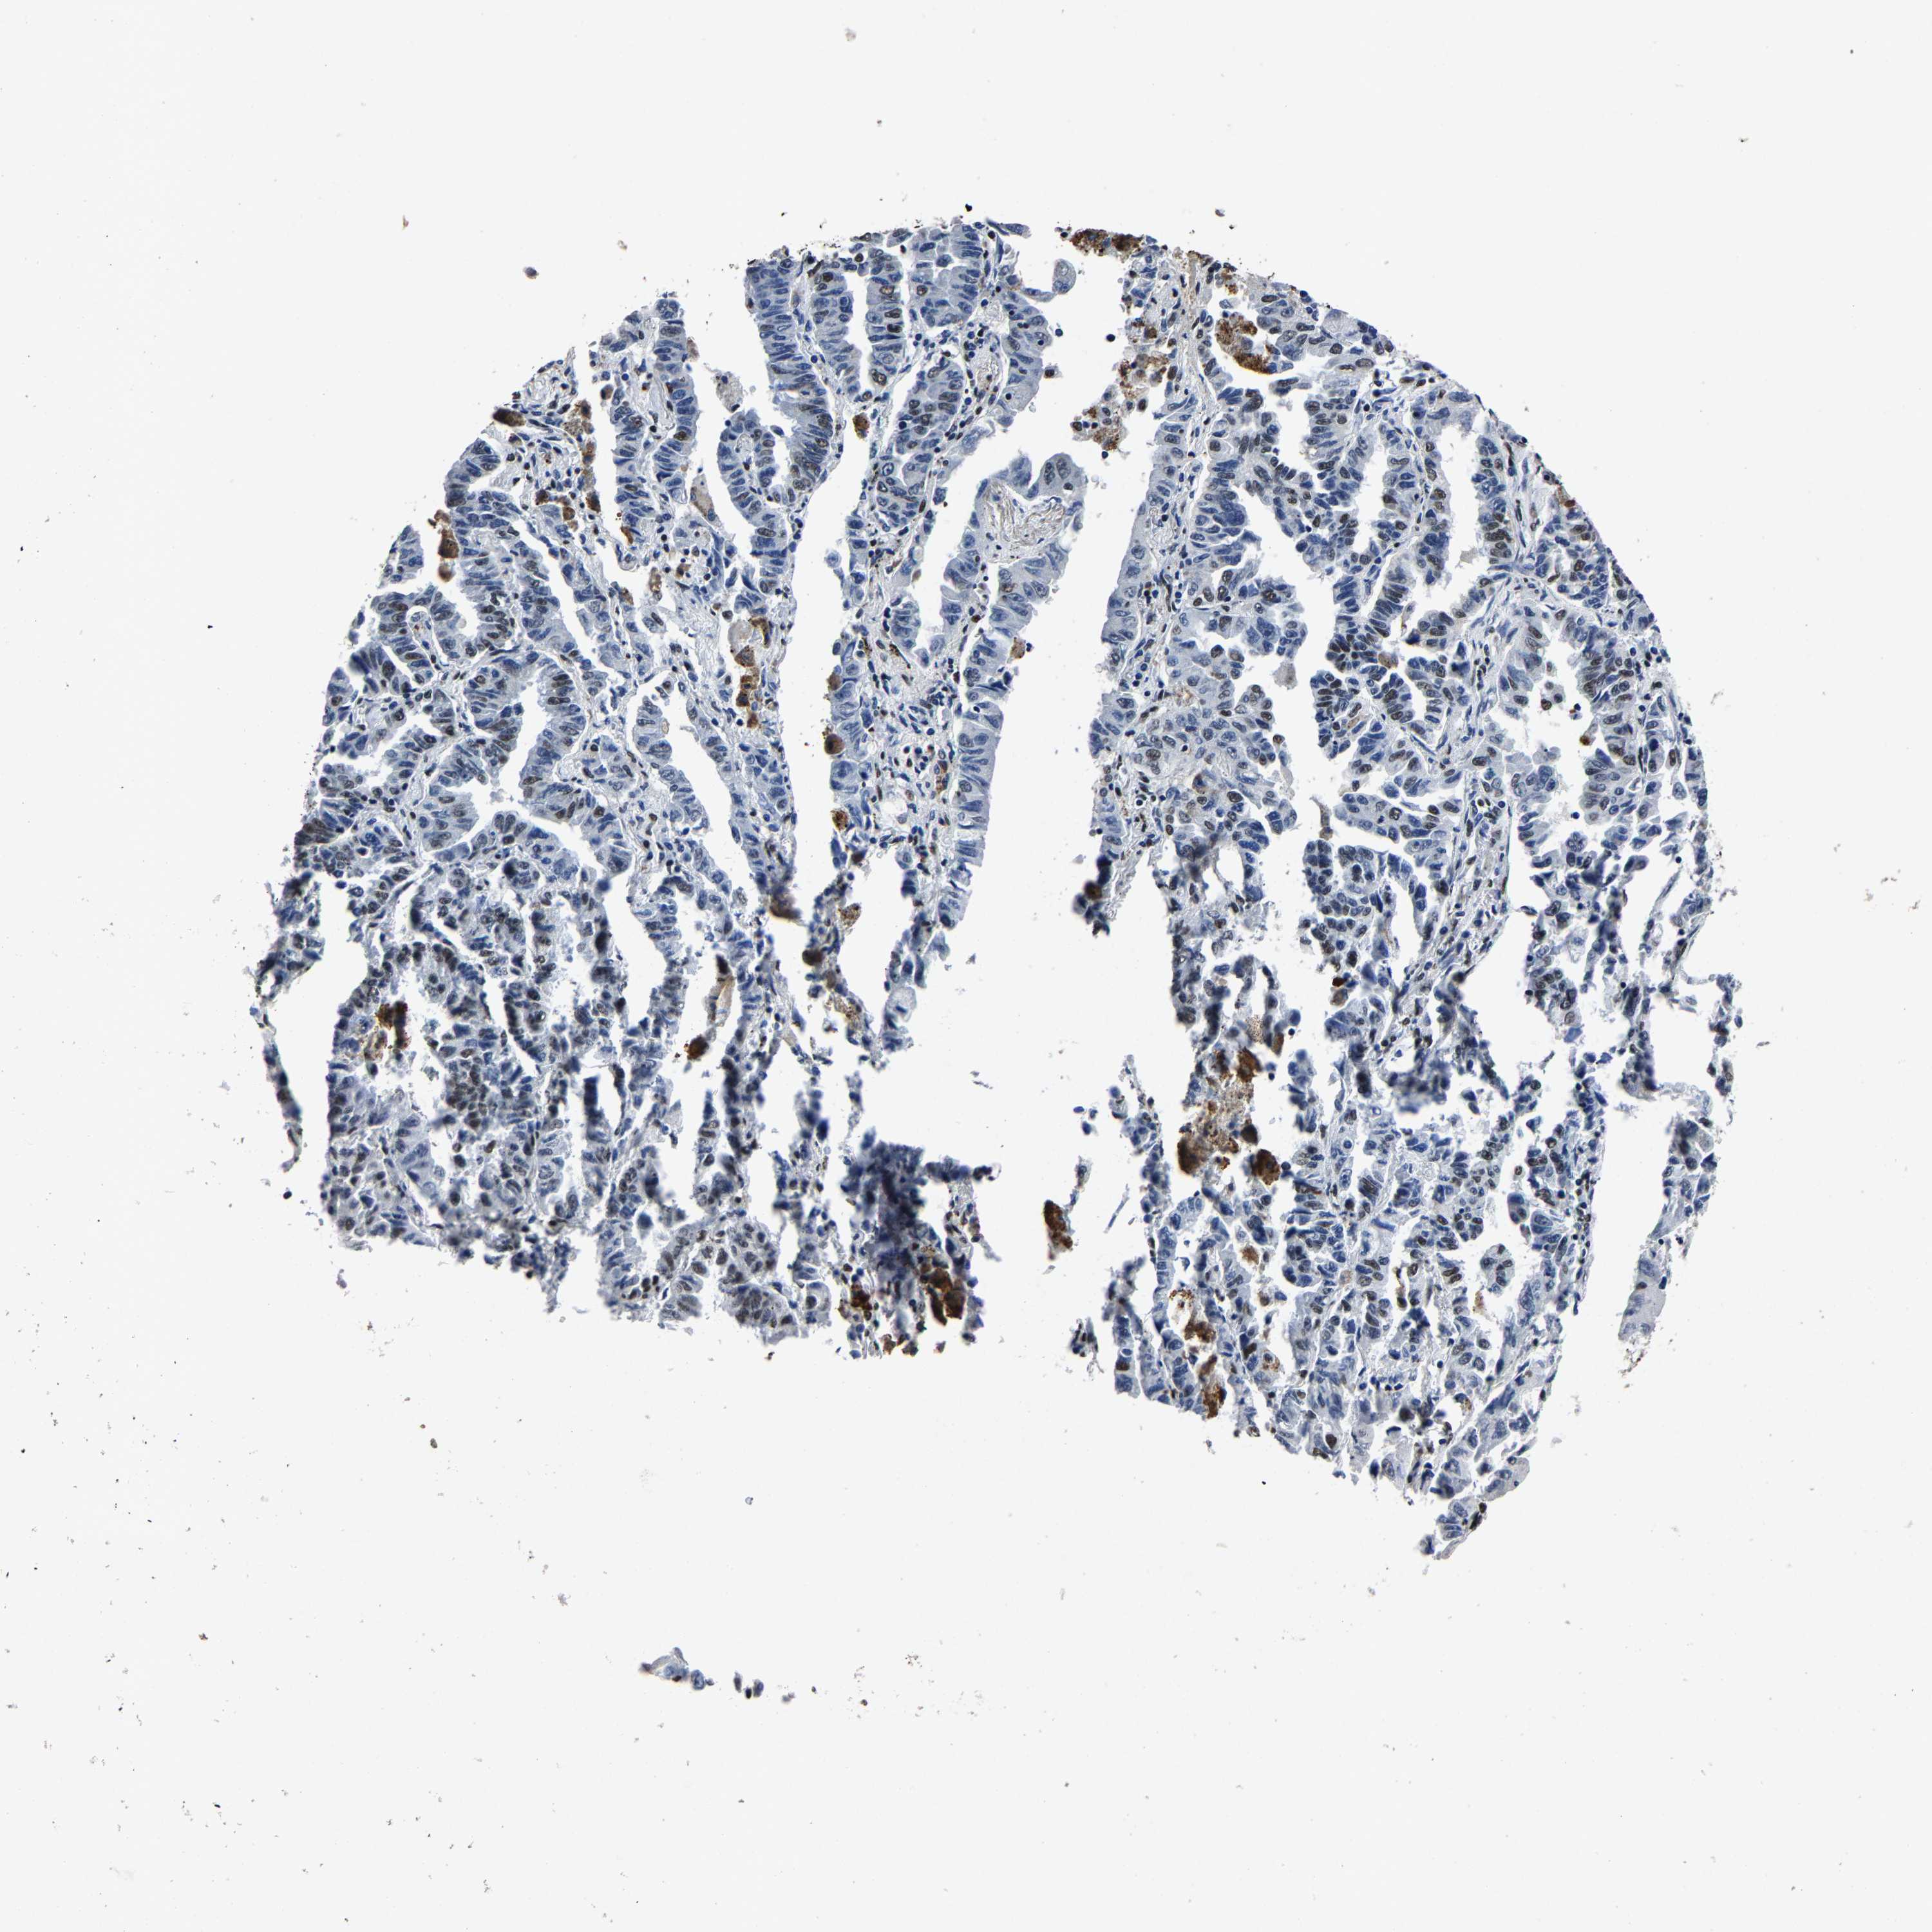

LUNG ADENOCARCINOMA (VALIDATION) - Interactive survival scatter ploti

The Survival Scatter plot shows the clinical status (i.e. dead or alive) for all individuals in the patient cohort, based on the same data that underlies the corresponding Kaplan-Meier plots. Patients that are alive at last time for follow-up are shown in blue and patients who have died during the study are shown in red.

The x-axis shows the expression levels (FPKM) of the investigated gene in the tumor tissue at the time of diagnosis. The y-axis shows the follow-up time after diagnosis (years). Both axes are complimented with kernel density curves demonstrating the data density over the axes. The top density plot shows the expression levels (FPKM) distribution among dead (red) and alive patients (blue). The right density plot shows the data density of the survived years of dead patients with high and low expression levels respectively, stratified using the cutoff indicated by the vertical dashed line through the Survival Scatter plot. This cutoff is automatically defined based on the FPKM cutoff that minimizes the p-score. The cutoff can be changed by dragging the vertical line or by entering a cutoff value in the square labeled "Current cut-off".

Under the Survival Scatter plot the p-score landscape (black curve; left axis) is shown together with dead median separation (red curve; right axis). Dead median separation is the difference in median mRNA expression between patients who have died with high and low expression, respectively. It is calculated as follows: median FPKM expression of dead patients with high expression - median FPKM expression of dead patients with low expression. This is intended to aid the user in visually exploring custom cutoffs and the associated p-scores and dead median separation.

Individual patient data is displayed and can be filtered by clicking on one or more of the category buttons on the top of the page. Categories describing expression level and patient information include: high, low, alive, dead, female, male and tumor stages. The scale of the x-axis can be toggled between linear and log-scale by clicking on the "x log" button. Mouse-over function shows TCGA ID, patient information and mRNA expression (FPKM) for each patient.

& Survival analysisi

Kaplan-Meier plots summarize results from analysis of correlation between mRNA expression level and patient survival. Patients were divided based on level of expression into one of the two groups "low" (under cut off) or "high" (over cut off). X-axis shows time for survival (years) and y-axis shows the probability of survival, where 1.0 corresponds to 100 percent.

RBM45 is not prognostic in Lung Adenocarcinoma (validation)

Best expression cut offi

Based on the FPKM value of each gene, patients were classified into two groups and association between prognosis (survival) and gene expression (FPKM) was examined. The best expression cut-off refers the FPKM value that yields maximal difference with regard to survival between the two groups at the lowest log-rank P-value. Best expression cut-off was selected based on survival analysis .

When clicking on this number, the vertical dashed line indicating cut-off, the interactive survival plot, and the Kaplan-Meier curve will be adjusted to show results based on the best expression cut-off.

: 9.03

P scorei

Log-rank P value for Kaplan-Meier plot showing results from analysis of correlation between mRNA expression level and patient survival.

N/A

TCGA RNA samplesi

RNA-seq data is reported as average FPKM (number Fragments Per Kilobase of exon per Million reads), generated by the The Cancer Genome Atlas (TCGA) .

Normal distribution across the dataset is visualized with box plots, shown as median and 25th and 75th percentiles. Points are displayed as outliers if they are above or below 1.5 times the interquartile range. FPKM values of the individual samples are presented next to the box plot.

Average pTPM 11.0

Number of samples 105